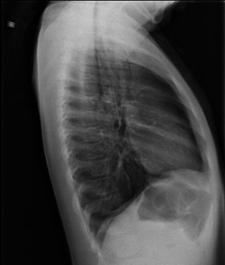

Hemo-pneumotorace stangDetaliu Fracturi costale multiple.Volet costal drept

Fracturi costale multiple  Hemitorace drept strivit

Volet costal si hemotorace

drept Fracturi costale multiple

Volet costal si hemotorace drept

Hemitorace drept strivit Hemitorace drept strivit Hemitorace drept strivit